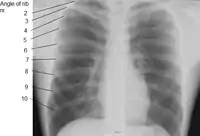

Human ribs are flat bones that form part of the rib cage to help protect internal organs. Humans usually have 24 ribs, in 12 pairs.[2] 1 in 500 people have an extra rib known as a cervical rib. People may have a cervical rib on the right, left or both sides.[3] All are attached at the back to the thoracic vertebrae and are numbered from 1 to 12 according to the vertebrae to which they attach. The first rib is attached to thoracic vertebra 1 (T1). At the front of the body, most of the ribs are joined by costal cartilage to the sternum. Ribs connect to vertebrae at the costovertebral joints.[4]

In general, human ribs increase in length from ribs 1 through 7 and decrease in length again through rib 12. Along with this change in size, the ribs become progressively oblique (slanted) from ribs 1 through 9, then less slanted through rib 12.[7]